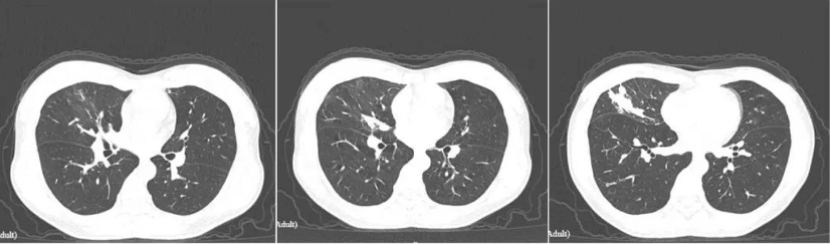

治疗一个半月后患者症状好转无其他不适,复查CT如下。